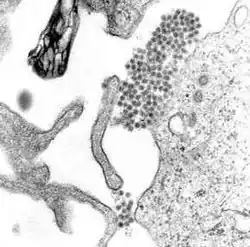

Virologia

O vírus da dengue (DENV) é um vírus RNA da família Flaviviridae; gênero Flavivirus. Entre outros membros do mesmo gênero estão os vírus da febre amarela, da febre do Nilo Ocidental, da encefalite de São Luís, encefalite japonesa, da encefalite transmitida por carrapatos, da doença da floresta de Kyasanur e da febre hemorrágica de Omsk. A maioria deles são transmitidos por artrópodes (mosquitos ou carrapatos) e, portanto, também são conhecidos como arbovírus, termo derivado da expressão em língua inglesa "arthropod-borne viruses".[11]

O genoma (material genético) do vírus da dengue contém cerca de 11 000 bases de nucleotídeos, que codificam três tipos diferentes de moléculas de proteínas (C, prM e E) que formam a partícula viral e sete outros tipos de moléculas de proteína (NS1, NS2A, NS2B, NS3, NS4A, NS4B e NS5) que apenas são encontradas em células hospedeiras infectadas e são necessárias para a replicação do vírus.[23][24] Existem quatro cepas do vírus, que são chamadas de serotipos, as quais são referidas como DEN-1, DEN-2, DEN-3 e DEN-4.[13] As distinções entre os serotipos baseia-se na sua antigenicidade.[25]